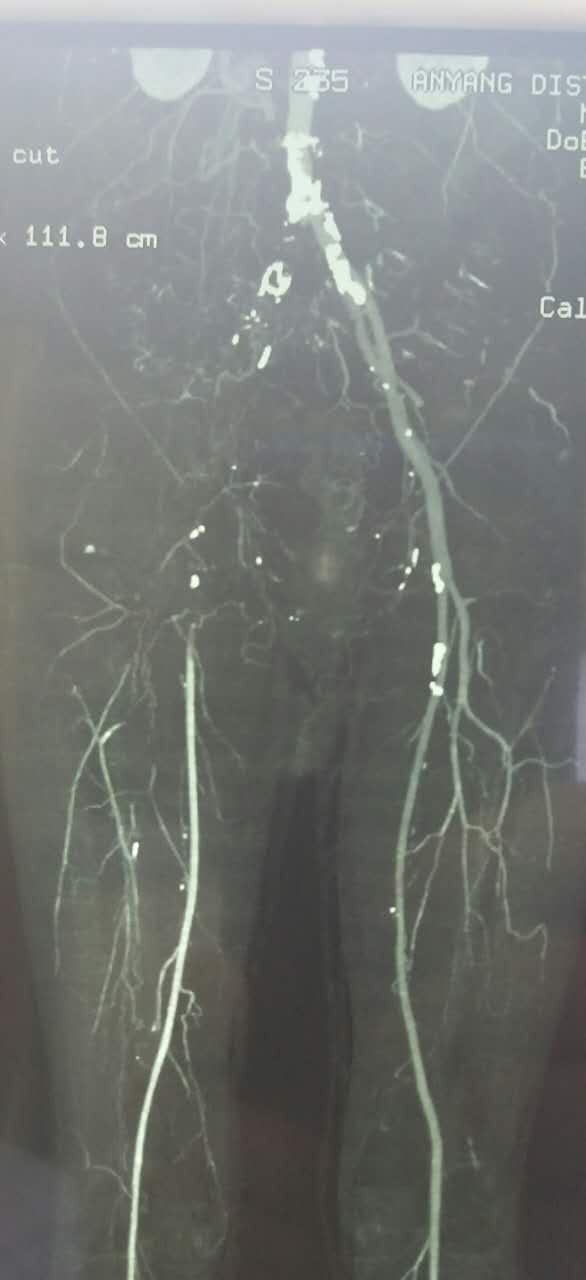

54岁男性,右足疼痛半月余。患者半月前无明显诱因突发右下肢疼痛,行走后加重,休息减轻。超声提示腹主动脉左髂动脉多发狭窄闭塞,右髂动静脉闭塞。CTA

入院后,结合病史,考虑有血栓形成的可能性,行全身静脉溶栓,一周后复查CT,右侧髂总动脉出现一段管腔

对比正常解剖模式图,我们可以发现:右侧髂总髂内髂外股总动脉未显影,股深动脉未显影,右侧股浅动脉起始段未见显影,考虑有血栓闭塞的可能。